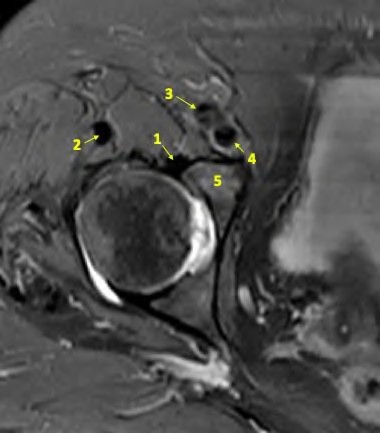

A 60-year-old male presents with groin pain 8 years after a metal-on-metal total hip arthroplasty. Lab results show elevated serum cobalt and chromium levels. MRI with MARS (Metal Artifact Reduction Sequence) shows a solid and cystic mass communicating with the joint space. What is the characteristic histological finding in the periprosthetic tissue of this condition?

Explanation